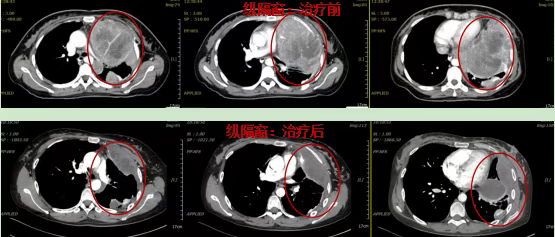

Mediastinal window findings:

Pre-treatment: The tumor occupied the entire left thoracic cavity, demonstrating significant mass effect with marked cardiac compression.

Post-treatment: The left lung showed re-expansion, with near-complete tumor regression and restoration of normal cardiac positioning.